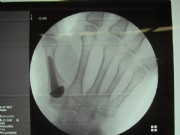

Middle and right: stiffening in the functional position with the V-tek regular screw. Eliminates pain and visually shows a satisfying result.

Below: End-joint stiffening in the index finger and middle-joint endoprosthesis in the middle finger